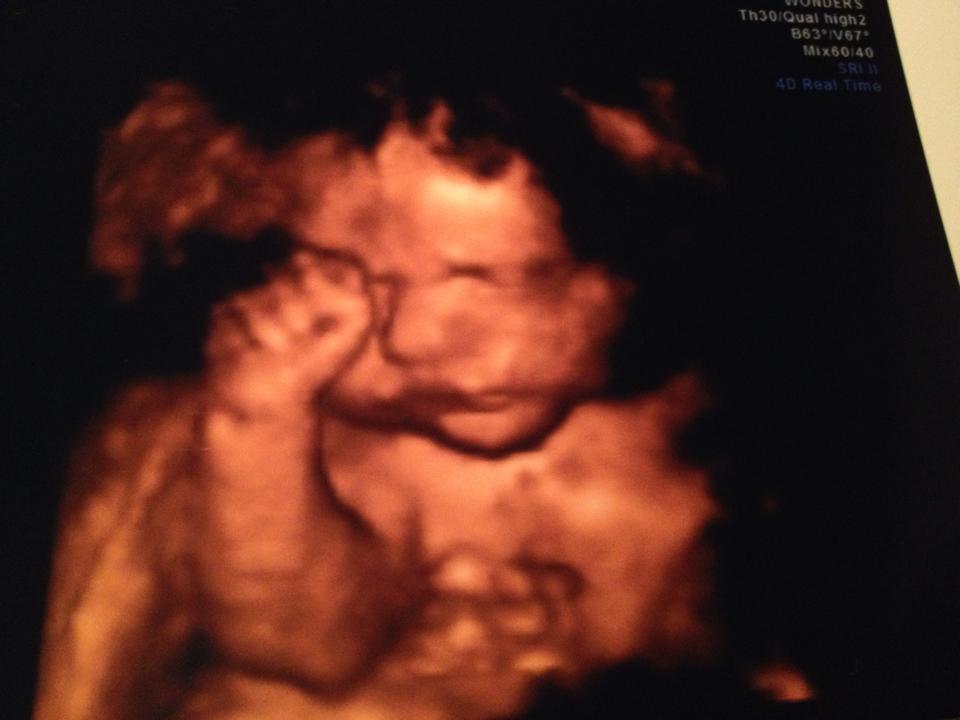

went for my 3D sono last night...

and cannot say enough good things about Little 3D Wonders. They were so friendly, didn't rush through, and the office made me feel so comfortable.

I went in thinking I was going to do a lower package and decided to go all out once I got in there…picture frame, stuffed animal with heartbeat, 1/2 hour package, etc.

I was also opposed to doing it in the beginning and wouldn't trade this experience for anything!

Here is my little girl (I can't stop staring)